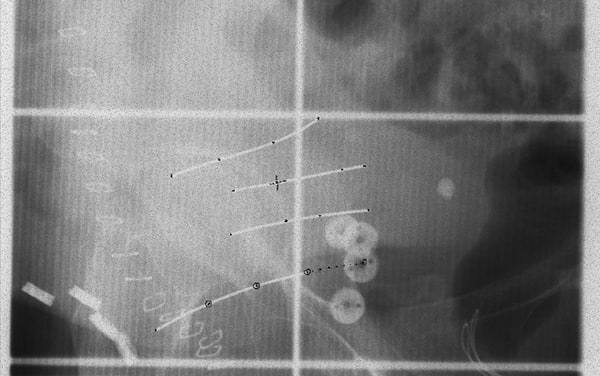

通过腹腔镜和膀胱镜联合,观察膀胱壁两侧。使用腹腔镜器械,清理膀胱壁以便后续插入导管,使用钛夹标记临床靶体积(CTV)边界,沿膀胱壁平行植入三至四根近距离治疗导管。导管两个末端均从患者皮肤中穿出